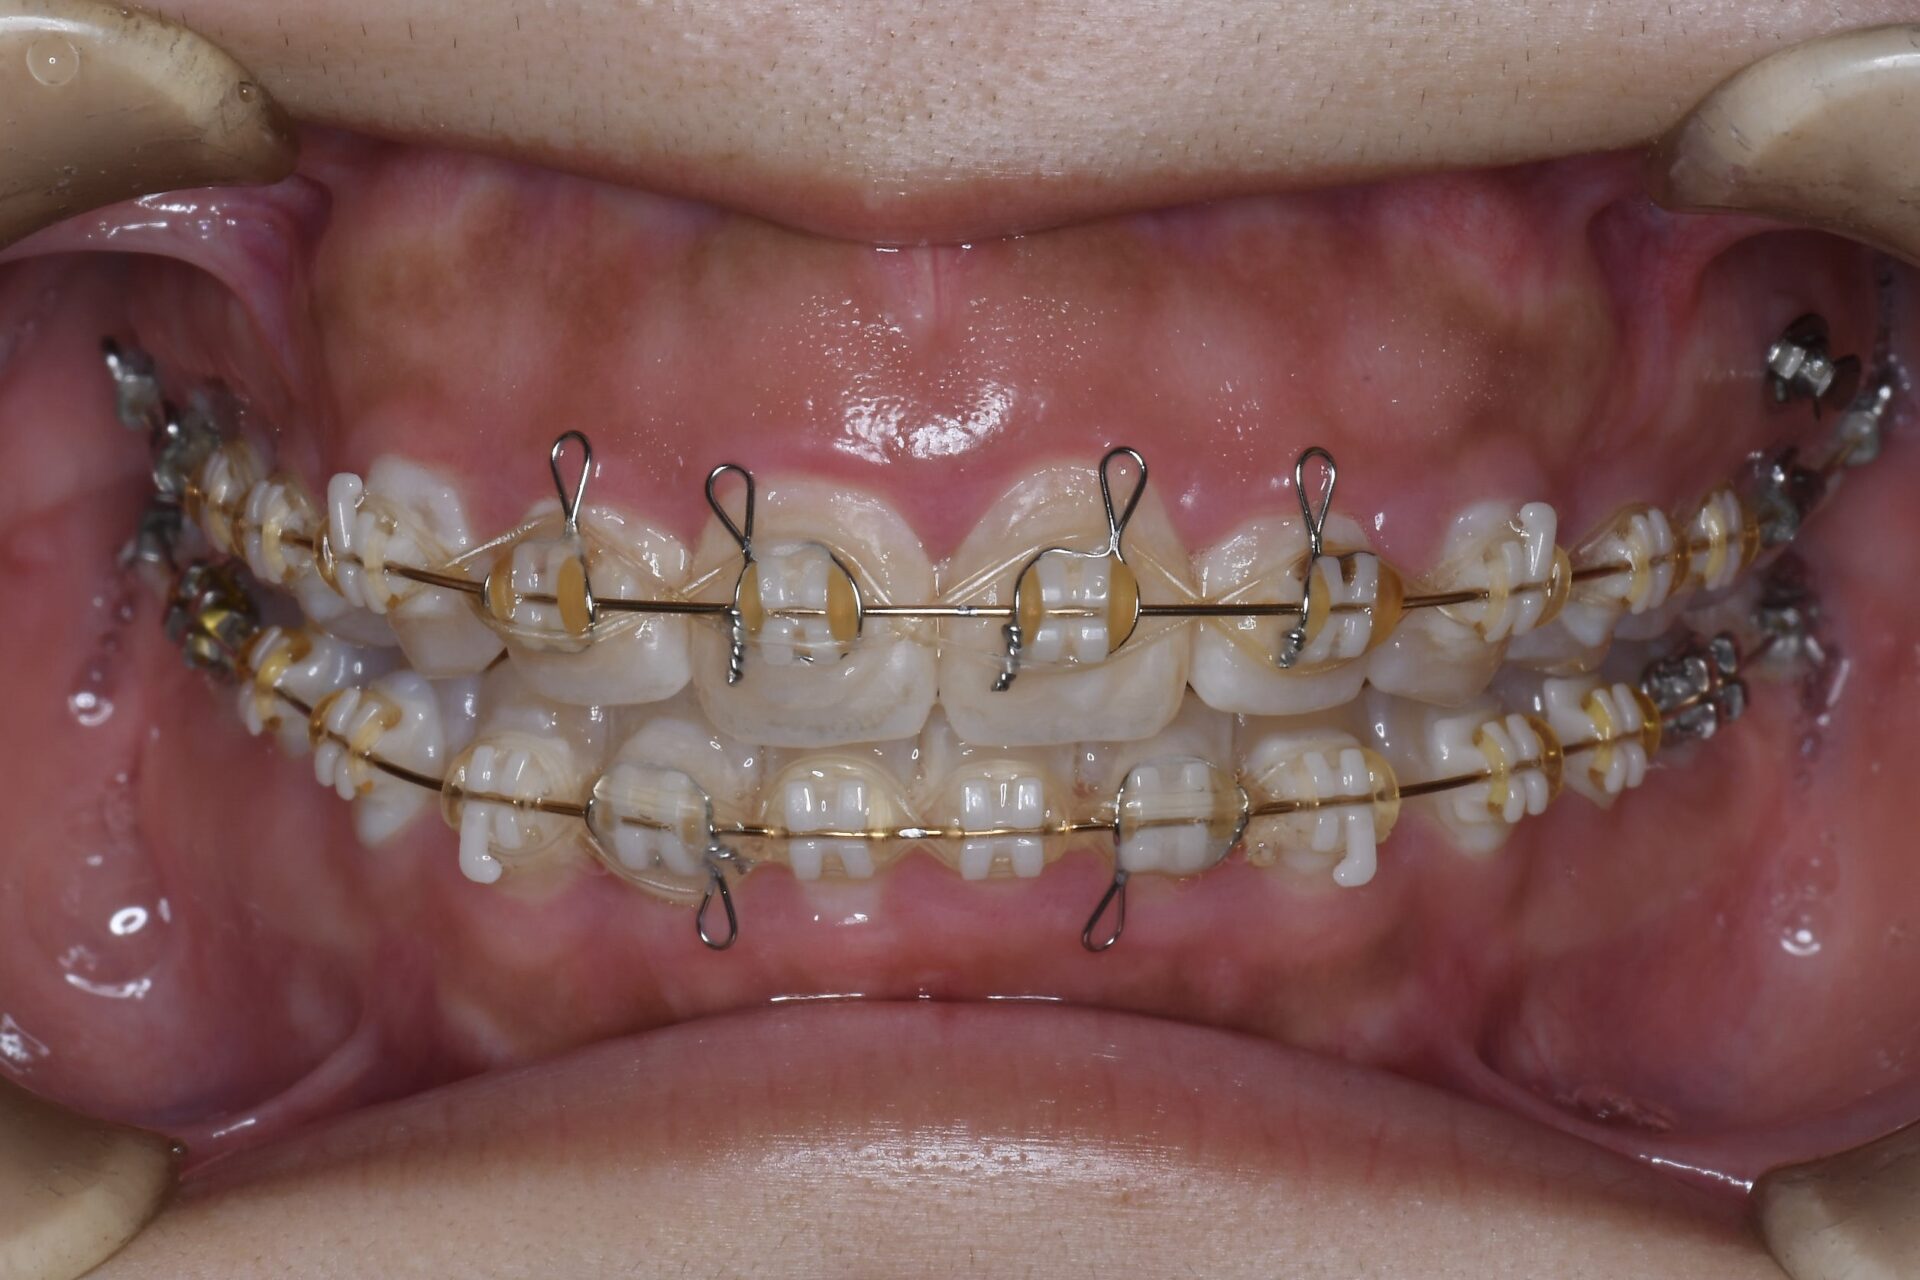

after

矯正治療終了時

親知らずを抜歯してそのスペースを利用して臼歯部を圧下しつつ、前歯の噛み合わせを近づけていく。